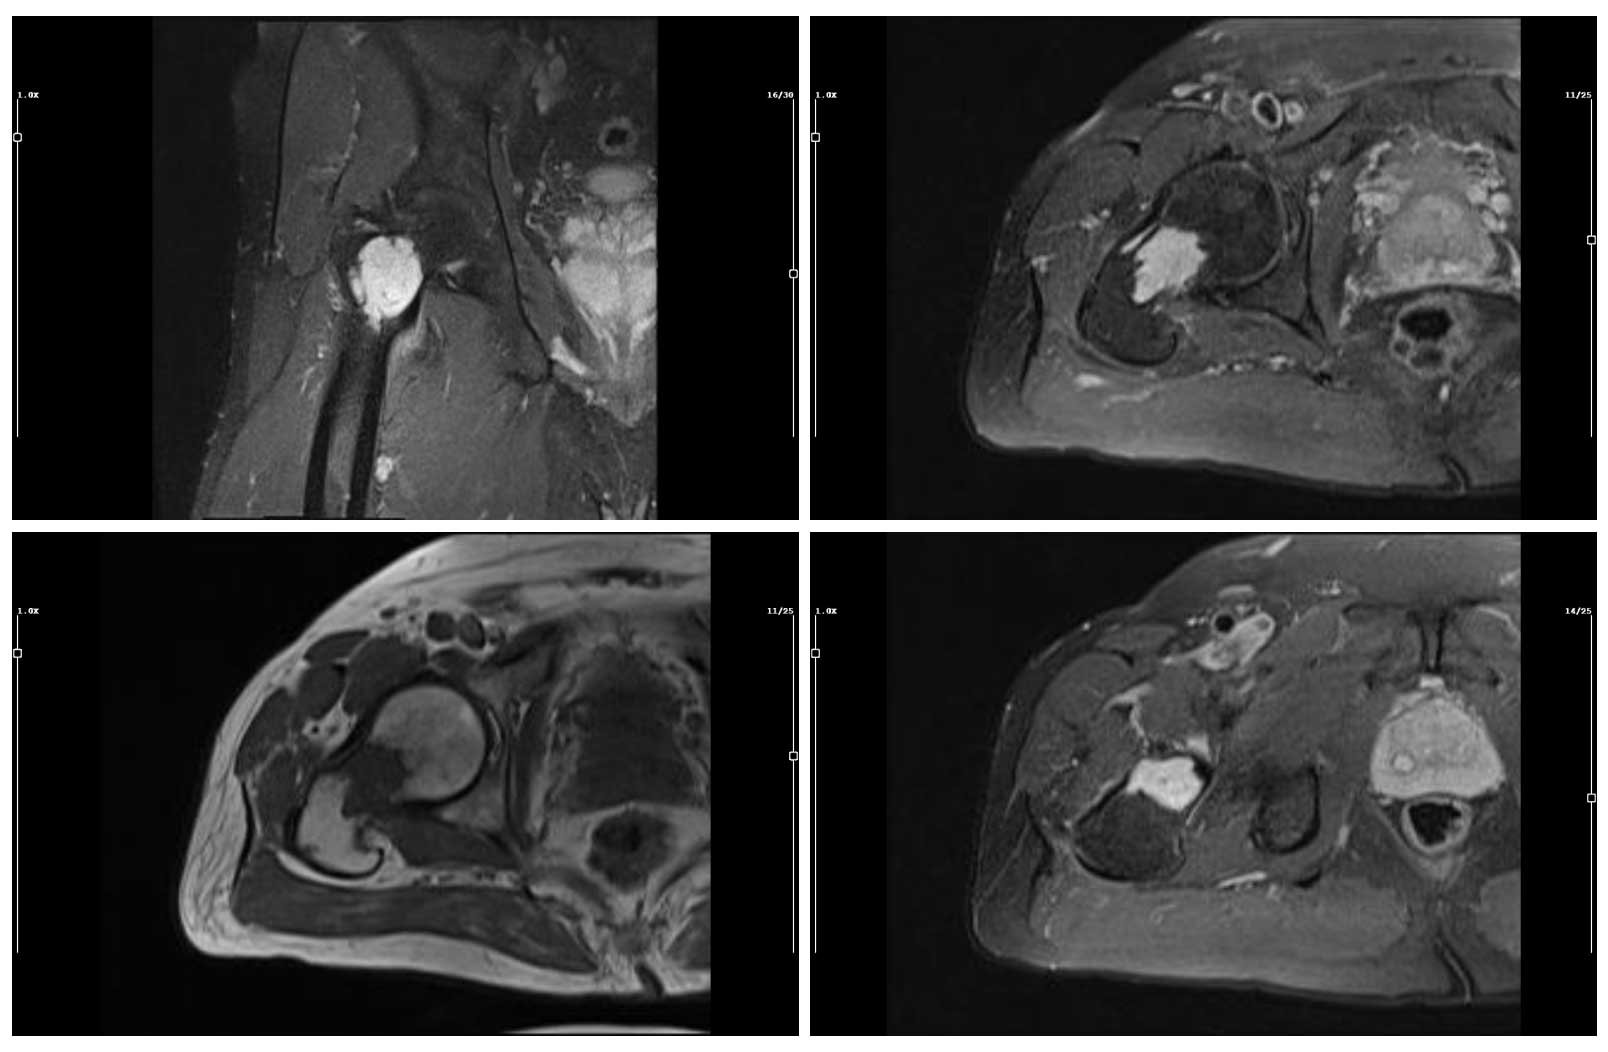

Ameliyat Öncesi: MR’da tümör sınırlarının düzensiz olduğu ve yoğun kontrast tuttuğu görülmekte.